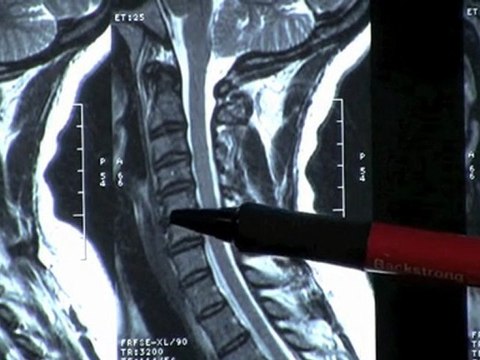

Spinal Decompression For Sciatica, Back & Neck Pain in Wood

bestatlantaspinaldecompression.com Help for Sciatica Back & Neck Pain.How to choose a spinal decompression center. Get a FREE e-book. the truth Spinal Decompression. Dont get ripped off!